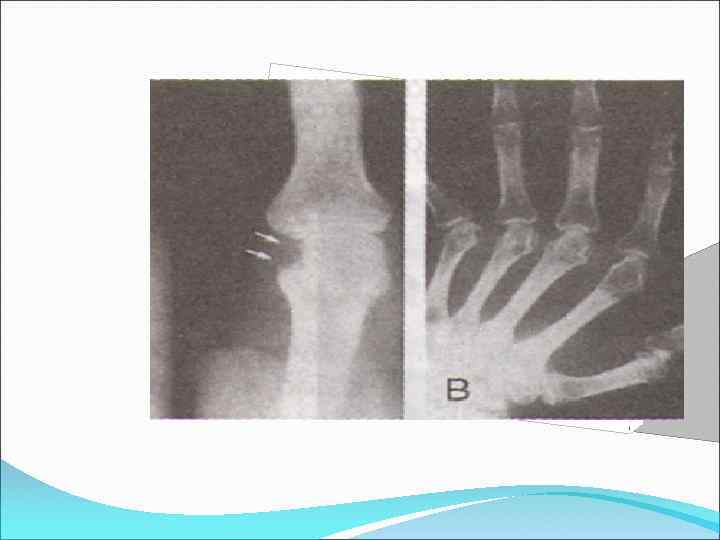

Рентгенологические стадии І – околосуставной остеопороз. Единичные кистовидные просветления костной ткани. Незначительное сужение суставных щелей в отдельных суставах ІІ – умеренный(выраженный) околосуставной остеопороз. Множественные кистовидные просветления костной ткани. Сужение суст. щелей. Единичные (1 -4) эрозии суставных поверхностей. Небольшие деформации костей. ІІІ – Умеренный (выр. ) околосуставной остеопороз. Множественные кистовидные просветления костной ткани. Сужение суставных щелей. Множественные (5 и более) эрозии суставных поверхностей. Множест. выраженные деформации костей, подвывихи и вывихи суставов ІV- Умеренный(выраженный) околосуставной (распростр. ) остеопороз. Множеств. кистовидные просветления костной ткани. Сужение суст. щелей. Множеств. эрозии костей и суст. поверхностей. Множеств. деформации костей. Подвывихи и вывихи. Костные анкилозы. Субхондральный остеосклероз Остеофиты на краях суст. поверхнстей.

Рентгенологические стадии І – околосуставной остеопороз. Единичные кистовидные просветления костной ткани. Незначительное сужение суставных щелей в отдельных суставах ІІ – умеренный(выраженный) околосуставной остеопороз. Множественные кистовидные просветления костной ткани. Сужение суст. щелей. Единичные (1 -4) эрозии суставных поверхностей. Небольшие деформации костей. ІІІ – Умеренный (выр. ) околосуставной остеопороз. Множественные кистовидные просветления костной ткани. Сужение суставных щелей. Множественные (5 и более) эрозии суставных поверхностей. Множест. выраженные деформации костей, подвывихи и вывихи суставов ІV- Умеренный(выраженный) околосуставной (распростр. ) остеопороз. Множеств. кистовидные просветления костной ткани. Сужение суст. щелей. Множеств. эрозии костей и суст. поверхностей. Множеств. деформации костей. Подвывихи и вывихи. Костные анкилозы. Субхондральный остеосклероз Остеофиты на краях суст. поверхнстей.